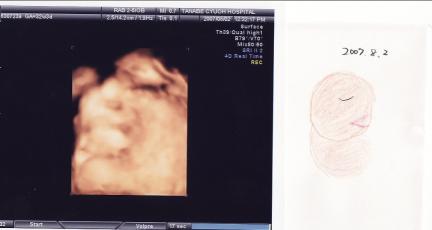

日時:2007年8月2日

場所:ママのおなかの中 (32週間と3日)

大きさ:BPD(頭の直径):8.39cm

FTA(腹部の断面積):55.56cm2

FL(大腿部の長さ)5.70cm

EFW(推定体重):1860g

う~ん、どんどん見にくくなってきた。

胎盤の位置と顔の位置が近いとキレイに写らないらしい。